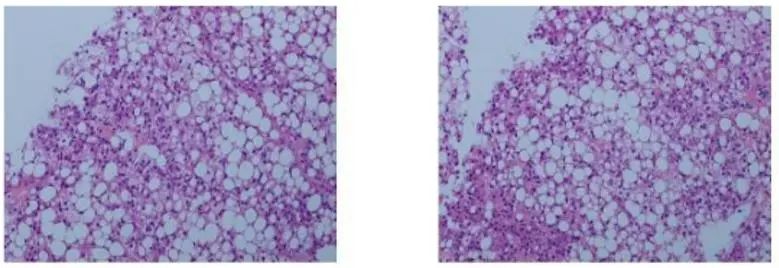

肝脏穿刺活检病理:

图3. 穿刺病理HE染色特征

④ H&E染色病理可见大量脂肪空泡,病因学角度提示HBV合并NALFD;

⑤ 免疫组化提示:CK7(1+), Ki-67(5%+);